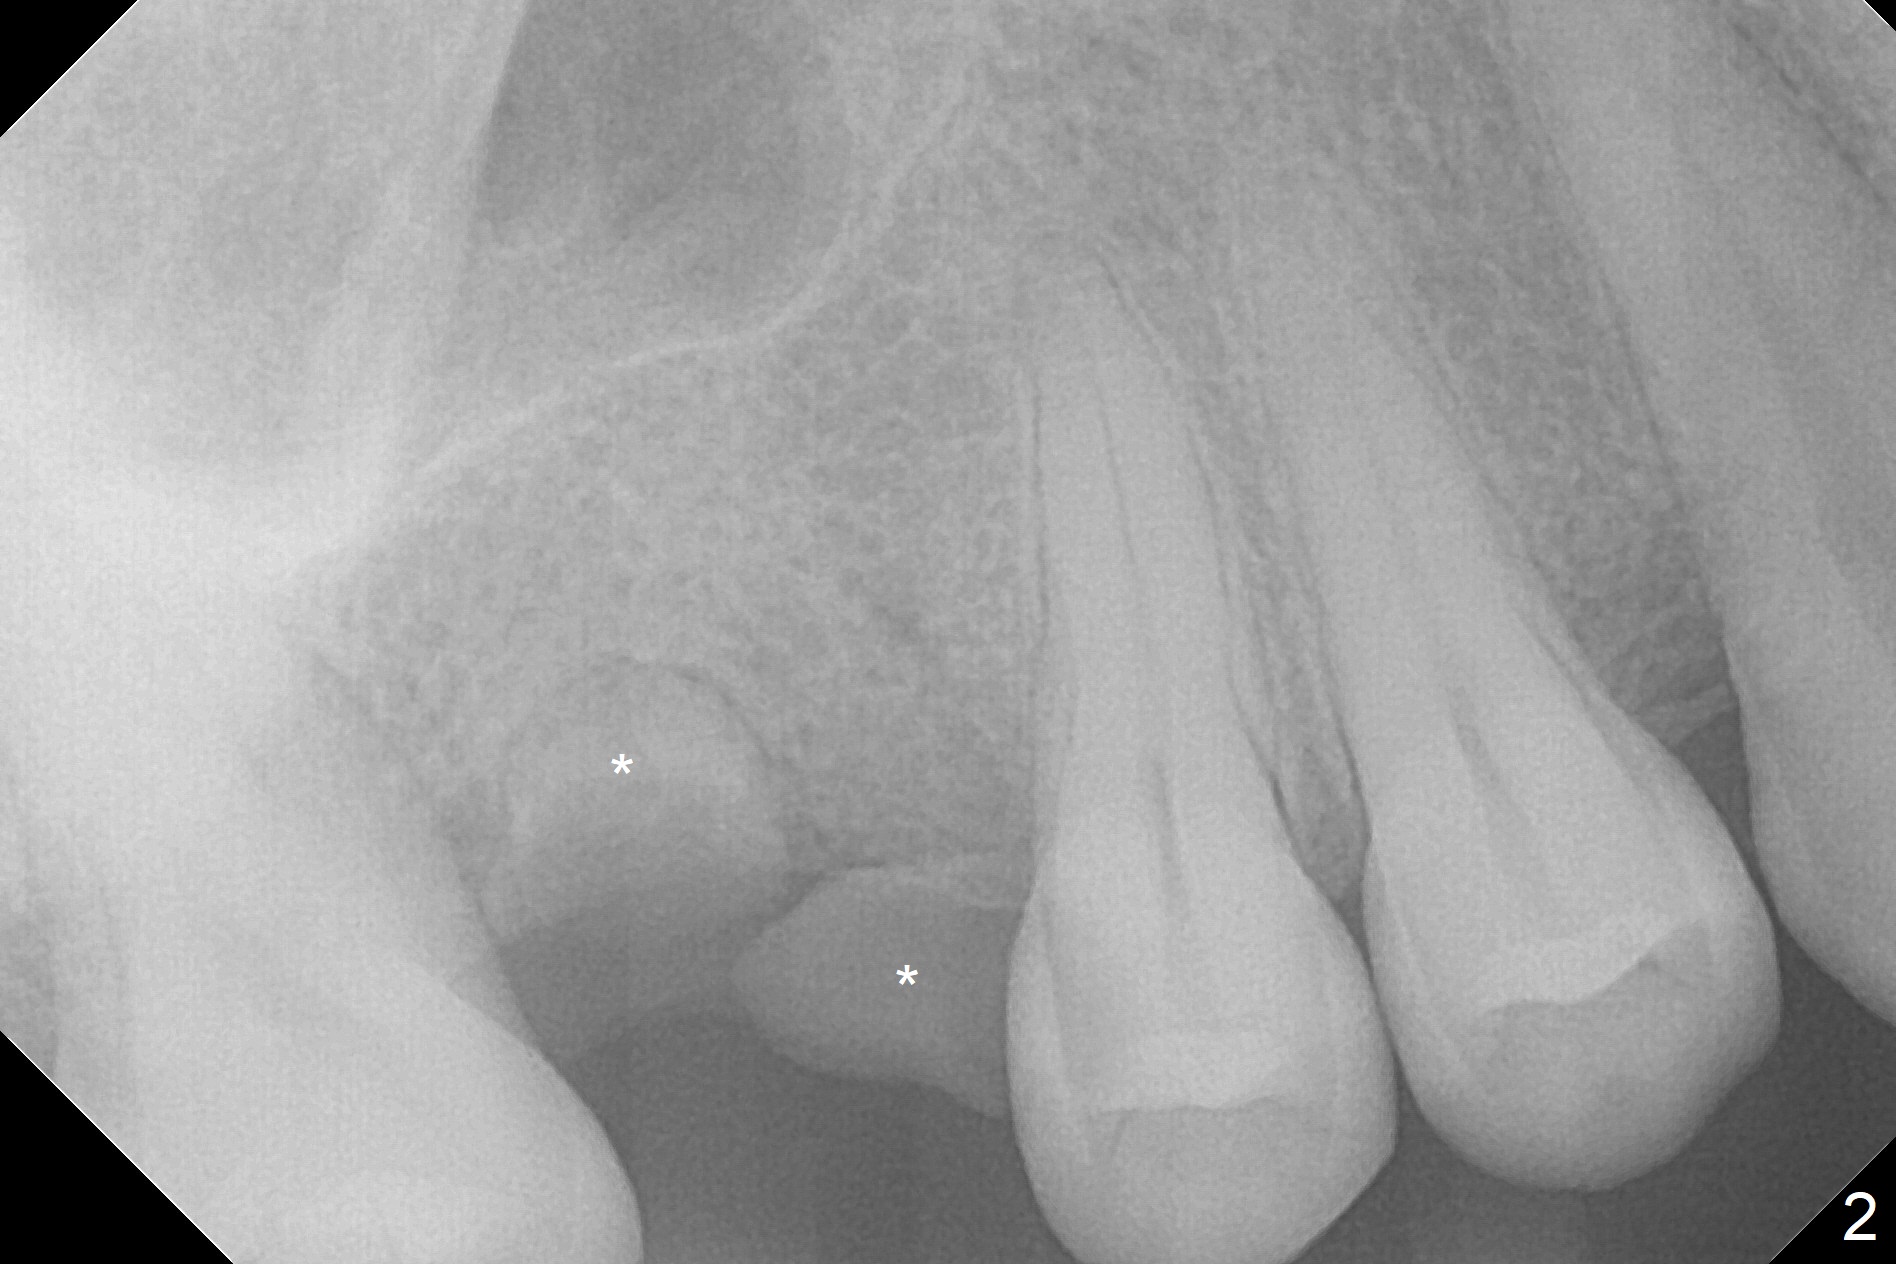

A 45-year-old woman has poor dentition due to dental phobia (Fig.1).  The tooth #3 has residual roots (Fig.2 *).  The initial depth will be 9 mm with starter drill, 2 mm drill (parallel pin, PA) and 3.2 mm Magic Drill (Fig.3).  Use 4x11 mm dummy implant for sinus lift for the last 2 mm.